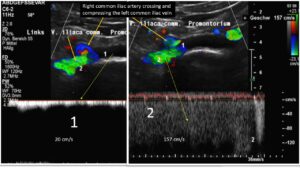

Further upstream the next outflow obstruction from the left leg is a May-Thurner syndrome due to a severe compression of the left common iliac vein: